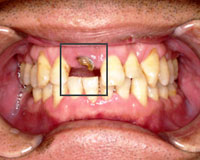

右上の前歯が抜けてしまい歯の根っこだけになっている患者さまの症例

治療前歯がほとんどなくなっていて根っこだけの状態。.

歯周病の進行と舌圧の強さにより、下の前歯が前に飛び出てきてしまい上の前歯とぶつかるようになってきた。そのため咬む力によって歯が欠けてしまっている。

また、歯と歯の間に隙間が拡がってきている。

原因は、歯周病の進行と、舌圧による咬合不全。